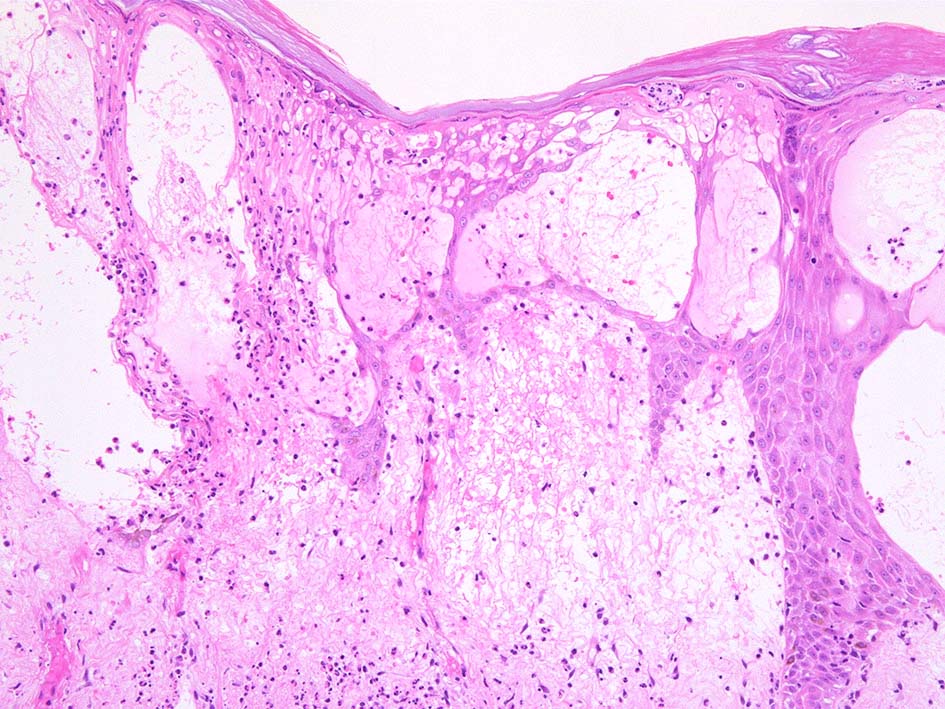

真皮上層浮腫がつよくなり表皮下水疱を形成することがある. 水疱内にはフィブリンや炎症細胞が多数認められる.

表皮基底層の液状変性, また液状変性ほど強くなくともvesicleの形成が見られることがある.

HE x40. Sweet病最盛期皮膚病変の所見があります.

表皮下水疱, 真皮上層の細血管周囲に密な好中球浸潤あり.(thumb nail clickで大きなphotoが見られます)